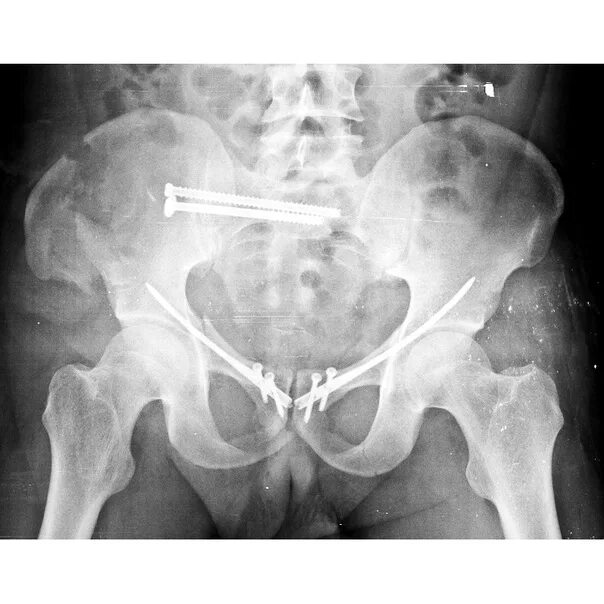

Боль в лонном сочленении